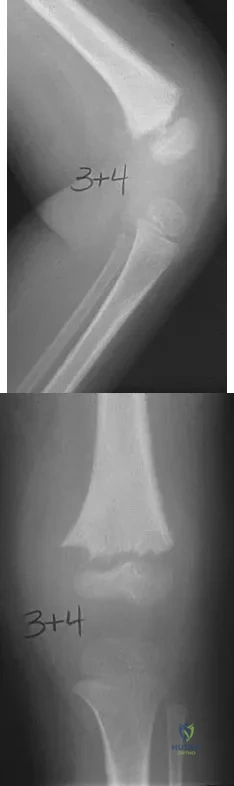

Examination of a 9-year-old girl who injured her left elbow in a fall reveals tenderness and swelling localized to the medial aspect of the elbow. Motor and sensory examinations of the hand are normal, and circulation is intact. A radiograph is seen in Figure 28. Management should consist of

Explanation

A 10-year-old boy has a painful, swollen knee after falling off his bicycle. Examination reveals no other injuries. Radiographs are shown in Figures 35a and 35b. Initial management of this fracture should consist of

Explanation